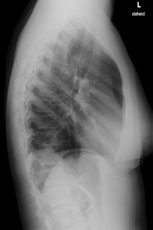

Eine 36-jährige Patientin kommt zu Ihnen in die Praxis. Sie berichtet über einen grippalen, fieberhaften Infekt, seit einer Woche bestehend.

In der Lungenauskultation sind Rasselgeräusche beidseits basal zu hören. Bei einem CRP von 160 mg/l veranlassen Sie ein Thoraxröntgen mit der Frage nach Infiltrat.

Hier sehen Sie die Bilder:

Thorax seitlich

Bild vergrössern